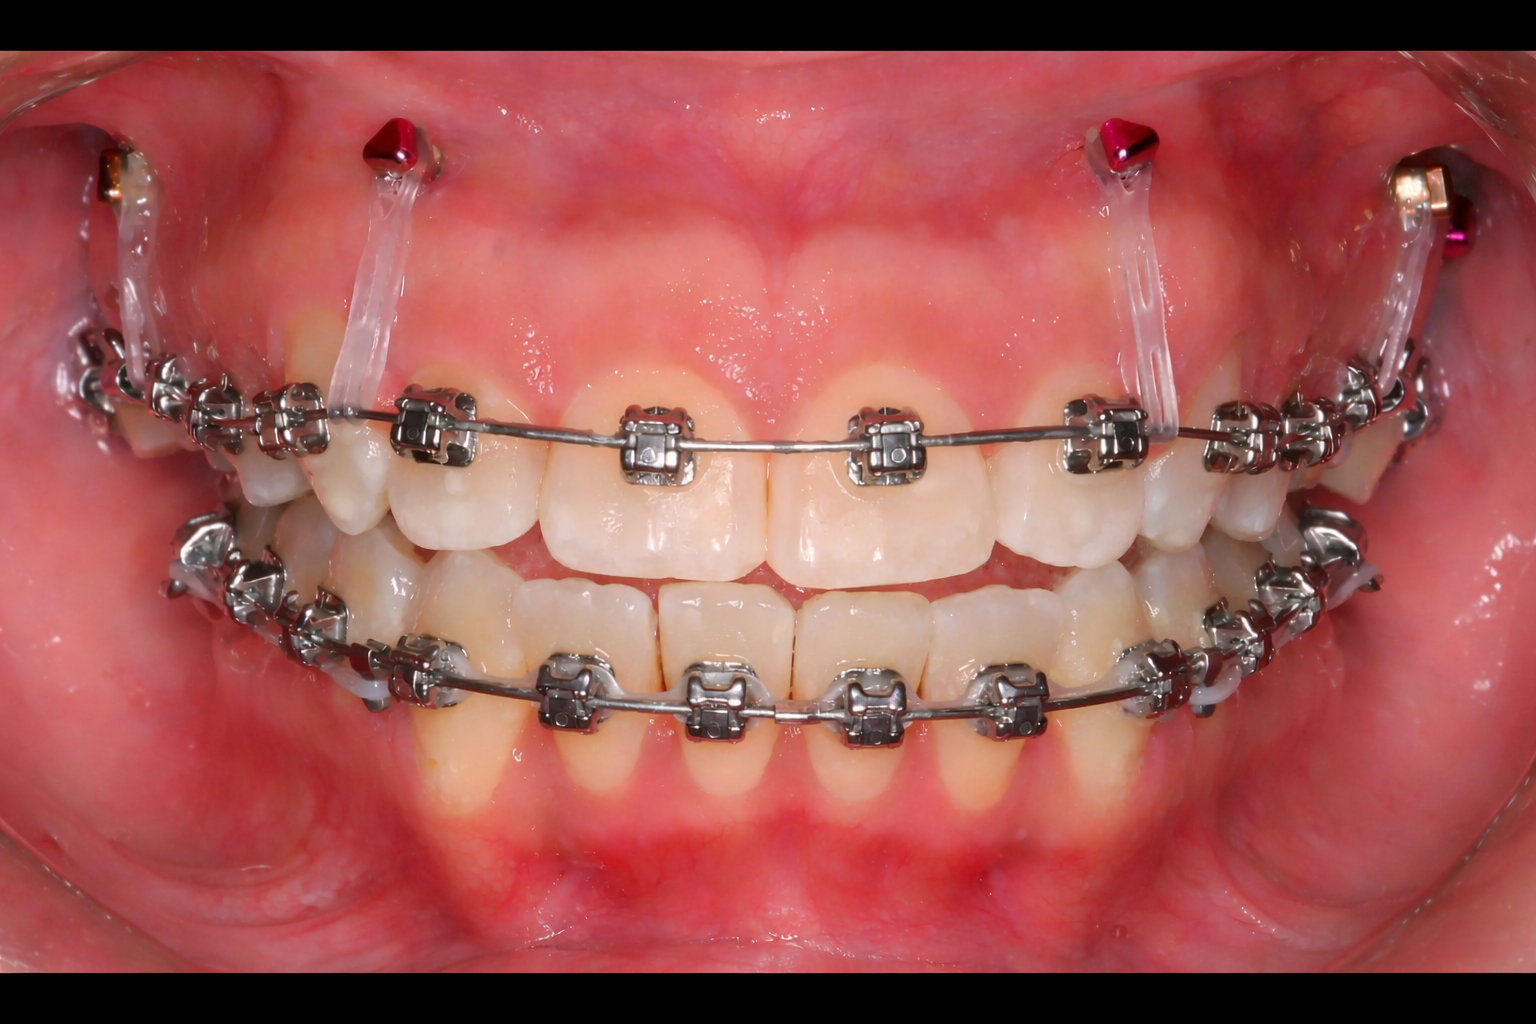

Mini-vis TAD pour béances antérieures avec broches

Béances antérieures

Les dents antérieures ne se touchent pas à la fermeture. L'approche traditionnelle nécessite souvent la chirurgie. Les TADs permettent l'intrusion des molaires pour fermer la béance sans chirurgie.